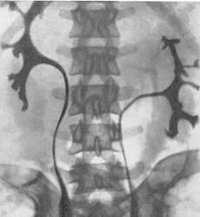

• Внутривенная пиелография:

о Срединное сращение:

- Чашечки как бы «держатся за руки»: нижние чашечки спускаются к средней линии около перешейка

- U-образная нефрограмма

- Редко чашечки от противоположных почек соединяются, образуя общую почечную лоханку с одним мочеточником

о Симптом «цветочной вазы»: каждый мочеточник пересекает перешеек, изгибается латерально и продолжается медиально (при нормальным ходе-дистально)

Диагностика

План диагностического обследования включает УЗИ, УЗДГ, экскреторную урографию либо ретроградную пиелографию, почечную артериографию, сцинтиграфию, компьютерную томографию. Урограммы позволяют рассмотреть низкое расположение органа, ограниченную подвижность, наслоение теней нижних полюсов почки на контур позвоночного столба, тень перешейка. При ретроградной пиелографии в первые минуты визуализируется четкий силуэт подковообразной почки и ее перешейка, низкое положение почечных лоханок, аномальное расположение чашечек.